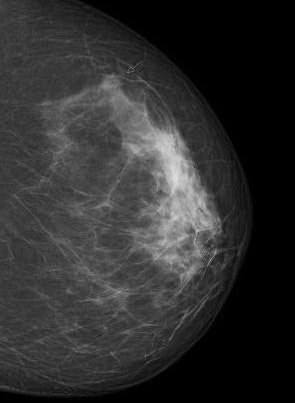

We need to start by explaining exactly what screening is: It's an initial search method that distinguishes between "normal" and "abnormal." An "abnormal" finding currently means the diagnosis has to be confirmed using additional methods. A screening mammogram doesn't clearly tell us whether the abnormality in the image is malignant, or why it's abnormal. If we eventually find it's benign, or there hasn't actually been a tissue change, we call it a false positive.

Any examination method can overlook a tumor, and this is something else you have to be open about. It's called a false-negative finding, and we can minimize it by using modern, proven mammography techniques and by providing special training for all screening teams, including radiologists and doctors. This is also why we use dual diagnosis: Each mammogram must be separately analyzed by at least two doctors. Two pairs of eyes are better than one, and this method gives at least a 15% increase in tumor detection rates than with one doctor.

And mammograms have their limitations when it comes to particularly dense tissue?

Yes, for women on the program who are ages 50 and older and have very dense type 4 breast tissue, although they really are the exception. Digital mammography, which is now standard in screening, penetrates dense tissue much better than analog x-rays 10 years ago.

We've just carried out a study in Münster of the density at which mammographic sensitivity declines. We found that contrary to what has been written elsewhere, sensitivity starts declining only with extremely dense type 4 tissue. We found no significant difference in sensitivity for women with a density of 1 to 3. Our study found the two-year interval screening mammogram program was significantly below average in only five percent of women. We need to consider giving them additional screening.